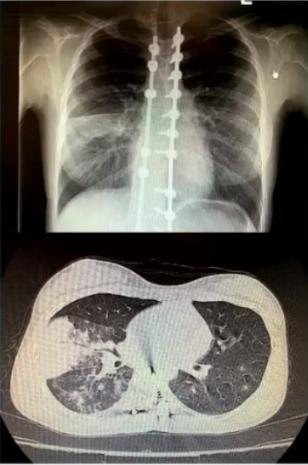

病例1

女性,15岁,既往曾行脊柱侧弯矫形术。因发热、咳嗽、咳黄痰1周入院。

发病后2天起予头孢曲松+阿奇霉素治疗至入院当日,日最高体温从39.9℃降至38.3℃,但发热、咳嗽、咳黄痰无进一步好转。

血常规检测:

• 发热第3天:WBC 5.34×109/L,N 0.659,CRP 1.063mg/dl

• 发热第7天:WBC 4.07×109/L,N 0.691,CRP 1.547mg/dl

CK 357.5 U/L,LDH 277.1 U/L

图1 患者的影像学以实变为主